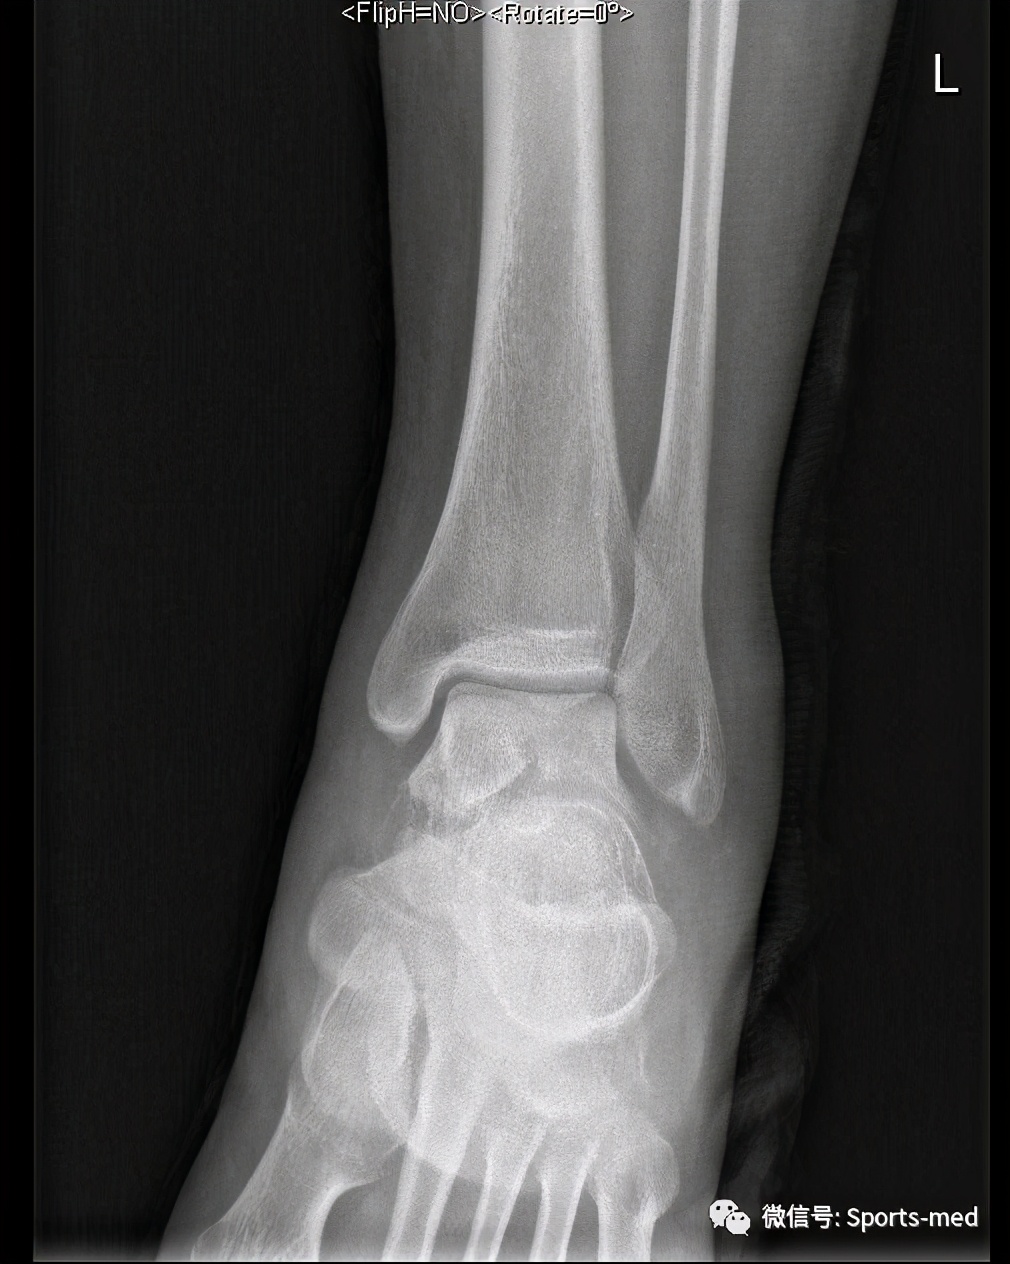

上周接诊了一位外地的患者,是一个28岁的男性患者,以打篮球时扭伤左踝关节为主诉来我院的,身高190,体重100kg的大只佬,受伤以后在当地医院拍了踝关节正侧位片,结果提示为距骨骨折(后方)

当地两家医院给出了两种方向的建议:切开手术治疗、打石膏保守治疗,同时主张手术的医生还告知了各种可能的风险,比如距骨坏死、移位、不愈合、皮肤坏死等,而主张保守治疗的医生之所以建议保守是因为:坏死机率和发生创伤性关节炎几率很高,做和不做差不太多,看到这个片子的第一眼,我并没有马上给我的治疗建议,而是先让他做一个踝关节三维ct,判断骨折情况,三维ct结果要比我们想象中的好很多,骨折块位置还好。